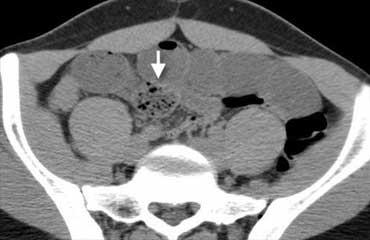

Tắc ruột cơ học. CT cho thấy các quai ruột non giãn, trong khi một phần ruột non và toàn bộ đại tràng không giãn. Do đó đây phải là tắc ruột non cơ học, và trong trường hợp này nguyên nhân có thể xác định dễ dàng: lồng ruột (đầu mũi tên).